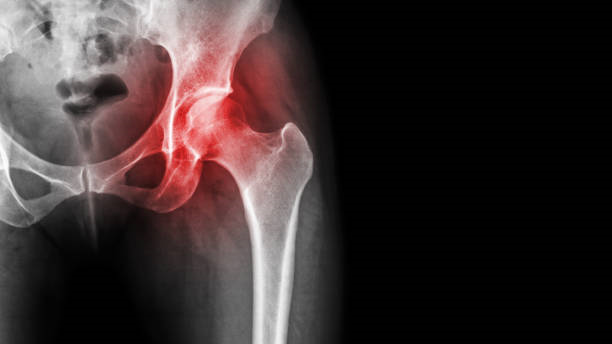

대퇴골두 무혈성괴사 (head of femur avascular necrosis 大腿骨頭無血性壞死)

대퇴골두의 혈관성 괴사, 일명 대퇴골두의 골괴사는 대퇴골에 대한 혈액 공급이 제대로 이루어지지 않아 조직 손상으로 이어지는 질환으로, 이 부위의 조직이 영향을 받게 되면 근육과 인대에 압력을 가하여 다리 저림, 얼얼함 등의 증상을 유발할 수 있습니다.

대퇴골두 무혈성괴사는 일반적으로 허벅지와 무릎 부위에서 다리저림을 느끼게 하고 다리의 무감각함과 따끔거림을 병행하기도 합니다.

대퇴골두 무혈성 괴사는 초기발견이 중요합니다. 조기 치료시에 예후가 많이 개선될 수 있다는 특징이 있습니다.